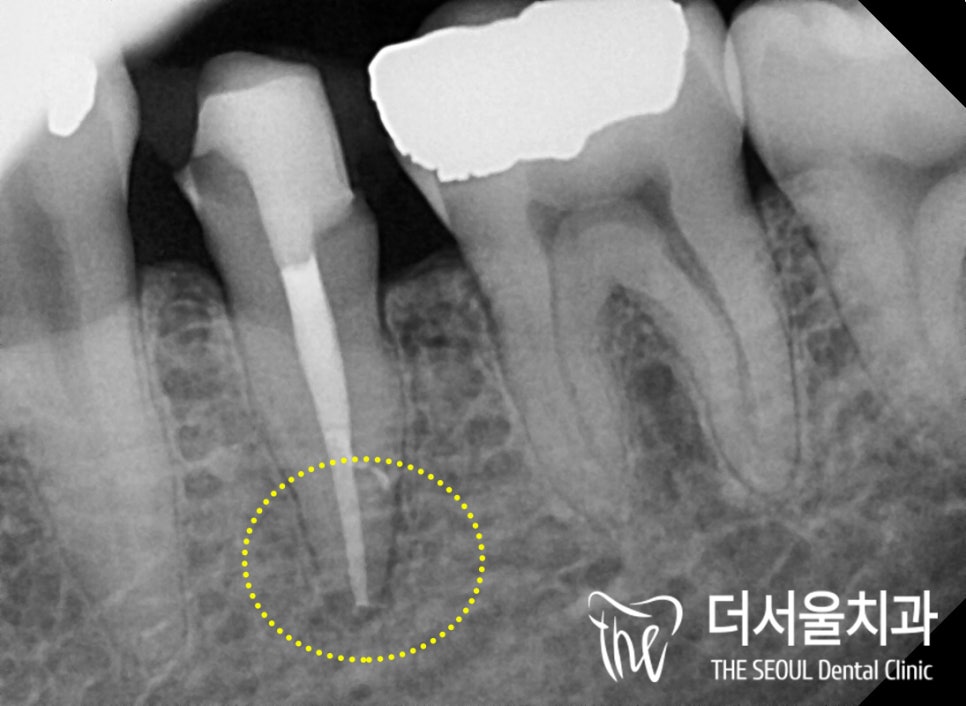

파노라마 사진을 찍어봤습니다.

어. 네.. 이미 이차충치 가 생겨있었네요.

치료를 받았던 곳이 또 한 번 썩은 것을

이차충치가 생겼다!라며 말하는데요.

딱 그 경우에 해당되었던 환자분,

감염의 크기가 심상치 않았는데요.

법랑질, 상아질을 지나

치수까지 감염이 일어나 있었습니다

주변 치조골을 봐도 별로 좋지 않다는 것을

한눈에 알 수 있을 만큼 말이죠.